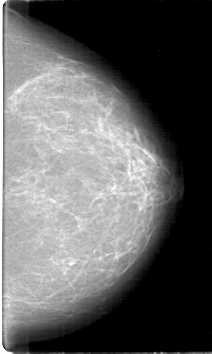

D_4126_1.LEFT_MLO

LEFT_MLO LINES 5281 PIXELS_PER_LINE 3091 BITS_PER_PIXEL 12 RESOLUTION 43.5 NON_OVERLAY